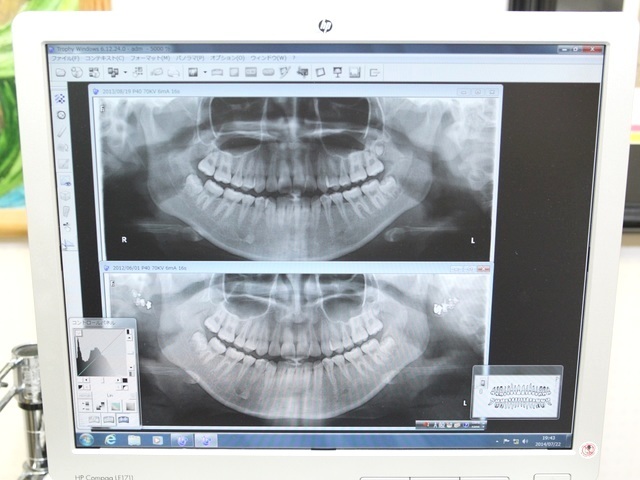

薬で治す歯周病治療を行っています

飲み薬やうがい薬を使って歯周病を治す、【歯周内科治療】を行っています。重度の歯周病でも、歯周外科手術(歯ぐきの手術)をせず治療ができ、痛みがなく患者さまにとって負担が軽い最新の歯周病治療法です。